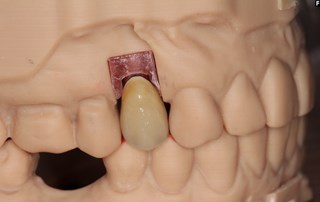

Våra tandtekniker på "Fenix Dentalteknik" i Örebro framställer en krona.

Kronan kan antingen monteras som på bilden med en centrumskruv alternativt cementeras fast på en distans.